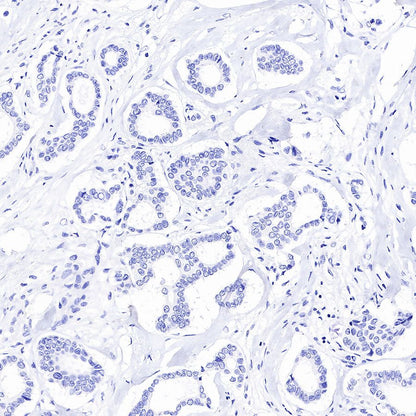

Immunohistochemistry

IHC shows positive staining in paraffin-embedded human prostate cancer. Anti-PSA antibody was used at 1/1000 dilution, followed by a HRP Polymer for Mouse & Rabbit IgG (ready to use). Counterstained with hematoxylin. Heat mediated antigen retrieval with Tris/EDTA buffer pH9.0 was performed before commencing with IHC staining protocol.